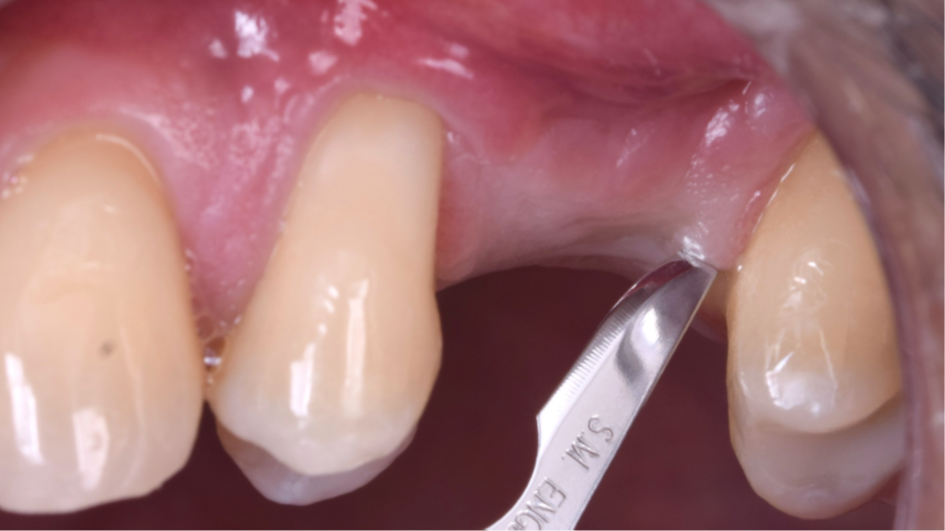

O presente trabalho tem como objetivo fazer um relato de caso clínico de reintervenção em enxerto ósseo para levantamento de seio maxilar pela técnica da janela lateral com instalação simultânea de implante Maestro Superiore.

Relato de Caso